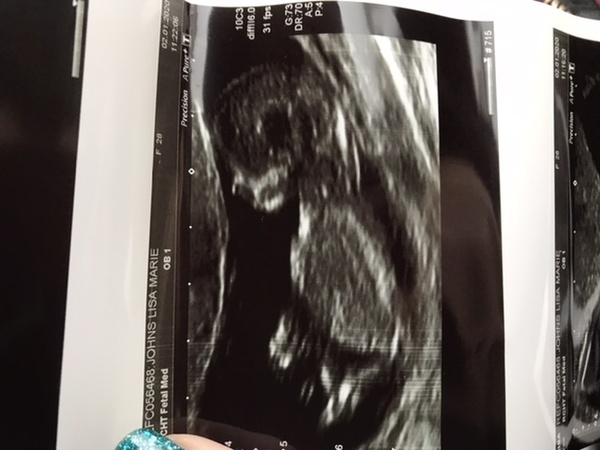

LisaxMarie · 02/01/2020 13:08

One very wriggly but healthy baby. Put us 2 days ahead so now 12+1 instead of 11+6!

So relieved! The sonography has me jumping up and down to try to get baby to turn around for the Nuchal test 😂

What a lovely picture @LisaxMarie

@LisaxMarie your scan pic is lovely 💕 Mine was similar - the sonographer had me wriggling from one side to the other to get baby to move lol. I had to half empty my bladder (not easy) and ended up doing some star jumps!